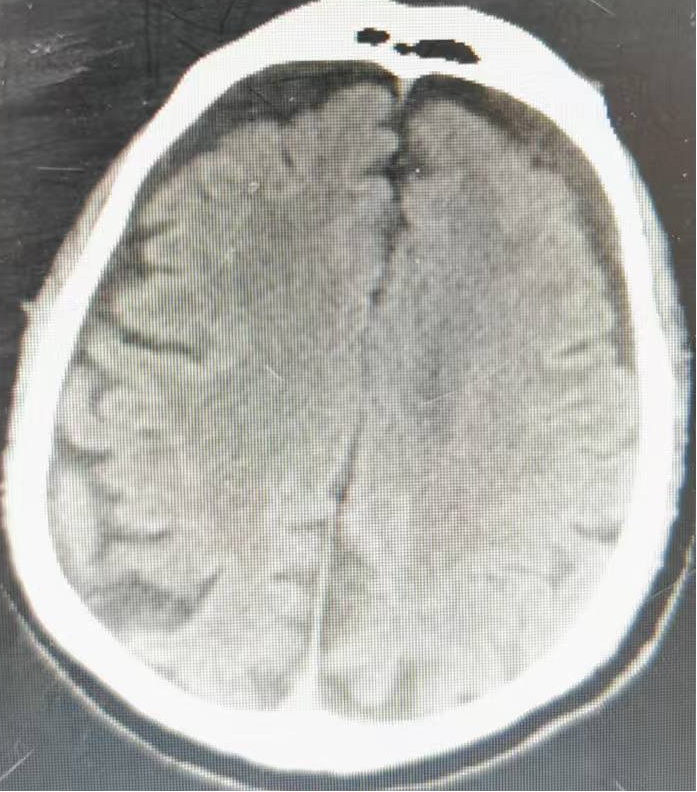

守护大脑健康 筑牢康复防线 ——神经内四科开展脑梗死专题患教会

为普及脑卒中防治知识,提升脑梗死患者及家属的居家康复能力及慢病管理水平,降低疾病复发风险,近日,济阳区人民医院神经内四科开展了脑梗死专题患教会。活动中,江新媛主任结合临床真实病例,以通俗易懂的语言,向...